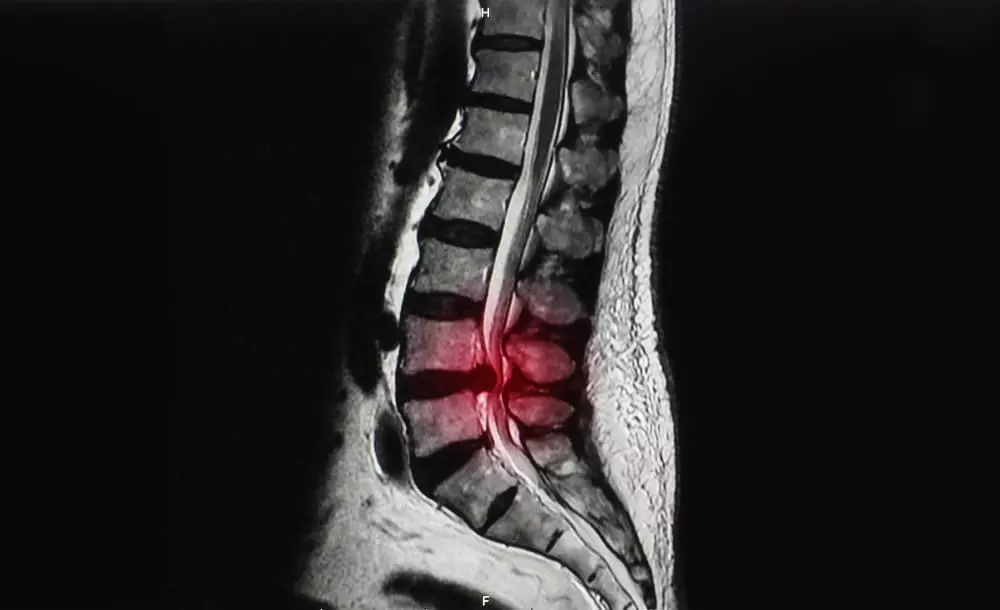

Before

After

脊柱管狭窄症とは?

体を支える脊柱は、椎骨という骨が連結してできています。

その椎骨には穴が存在し、脊柱として形成されたときには脊柱管という脊髄・血管が走る道が作られます。

その脊柱管が加齢や何かの要因でズレが生じ狭まったときに発症するのが脊柱管狭窄症です。

脊柱管が狭くなると、内部を走っている脊髄や血管が押し付けられます。

それにより

痛みやしびれといった症状が現れます。